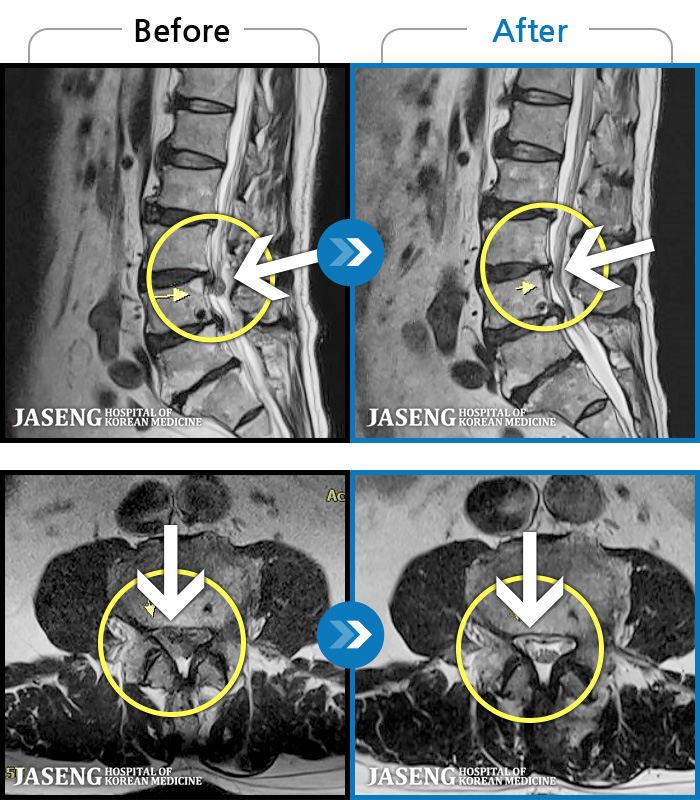

Before

After

허리부터 골반이 묵직하고 뻐근한 통증, 우측 허벅지까지 이어지는 저림 증상으로 내원하셨습니다.

2025.01.20 ~ 2025.10.25